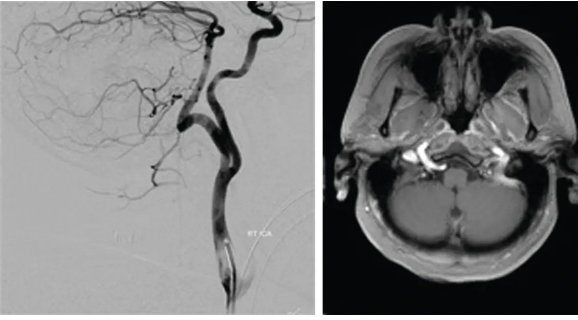

An angiogram and MR image of the brain are shown. Which of the following vessels supplies the posterior circulation in this patient?

A. Fetal posterior communicating artery

B. Persistent hypoglossal artery

C. Persistent otic artery

D. Persistent proatlantal segmental artery

E. Persistent trigeminal artery

A